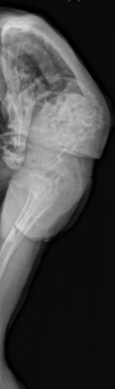

思春期特発性側弯症が高度に進行した症例です。最大側弯角度は113°であり、100°を超える側弯の手術は一般的に神経合併症が危惧されます。神経合併症を極力防ぐため、また侵襲を低減する目的で、同じ入院期間に2回に分けて段階的に矯正手術を行いました。1回目に最も側弯の強い箇所に対して側方から椎体間解離を行い、2回目に後方から全体のバランスが良くなるように慎重に矯正固定術を施行しています。

神経合併症はなく、術後の最大側弯角度は15°に改善(矯正率:87%)、背中の大きなコブも無くなっているのが分かります(赤矢印)。神経合併症が発生しないように慎重に手術を行うのは当然ですが、側弯を治すだけでなく横から見た姿勢を治すことにも留意しています。